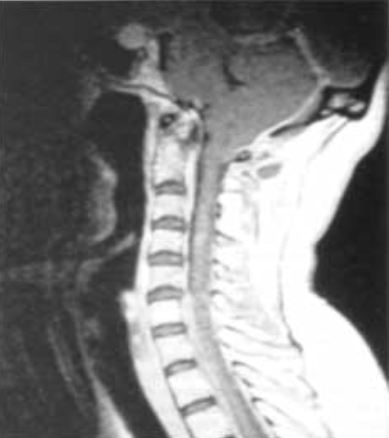

Se trata de la herniación en sentido caudal de las amígdalas cerebelosas y del tejido cerebeloso en el canal cervical (Fig. nº 2). Puede producir una dificultad en el drenaje del líquido cefalorraquídeo a través del techo del IVº ventrículo que se deforma al ser arrastrado caudalmente. En casos extremos puede producir hidrocefalia.

Figura nº 2. Cortesía del Dr. Royo-Salvador. RMN cervical de una paciente con una malformación de ARCH. Se observa la migración de las amígdalas cerebelosas al interior del canal cervical, por debajo del "foramen magnum".